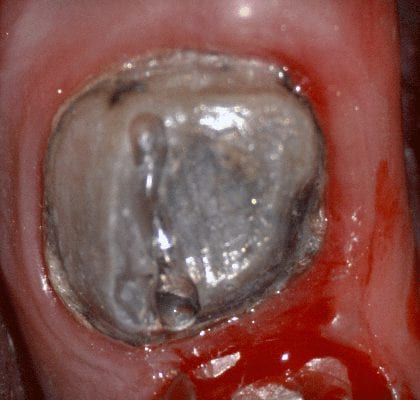

In this video we demonstrate some of the most common problems associated with second molar impressions. Usually the distal margins can be blurred by the presence of hemorrhaging or soft tissue. In this particular case, we use the tip of the camera to displace the tissue and digitall correct an area for better accuracy. The isolite systemisolite systemisolite system does a great job controlling the tongue and the lips and with proper retraction you can image a quadrant in very little time